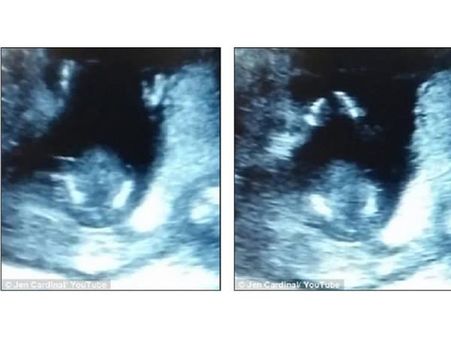

Baby With The Clapping Hands

Jen Cardinal uploaded a video of her ultrasound which showed her unborn child clapping his hands. The unborn kid was just 14-week old. The movement of the baby will give you goosebumps for sure when you watch the video online.